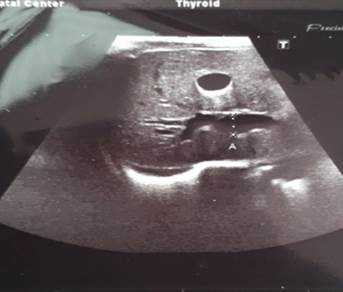

Ребенок Г. от 2-й беременности, протекавшей на фоне анемии, ожирения 2-й степени, угрозы преждевременных родов в 28 и 35 недель, плацентарных нарушений. Роды на сроке в 37 недель путем кесарева сечения. Оценка по шкале APGAR 8/8 баллов. За время наблюдения в первые сутки состояние ребенка с отрицательной динамикой за счет появления признаков церебральной возбудимости: вялое сосание, частые срыгивания, тремор подбородка при плаче. При осмотре кожный покров и видимые слизистые ярко-розовые, чистые, нормальной влажности. Аускультативно дыхание пуэрильное, проводится по всем полям, хрипов нет, ЧД 46 в минуту. Тоны сердца достаточной громкости, ритм правильный, ЧСС 140 уд/мин. Живот мягкий, не вздут. При пальпации печень и селезенка не увеличены. Физиологические отправления не нарушены. Ребенок переведен в отделение патологии новорожденных и недоношенных детей (ОПННД) на дообследование и лечение с предварительным диагнозом: Церебральная возбудимость. В ОПННД был проведен ряд обследований для уточнения диагноза. В общем анализе крови отклонений не выявлено: эритроциты 4,5х1012/л, гемоглобин 128 г/л, лейкоциты 13,2х109/л, нейтрофилы сегментоядерные 53 %, лимфоциты 38%, эозинофилы 2%, моноциты 6%, базофилы 1%, тромбоциты 337х109/л. В биохимическом анализе крови отмечаются: незначительное снижение общего белка - 55,8 г/л (норма 66-88 г/л), повышение уровня АСТ до 50,9 ед/л (норма до 37 ед/л), общего билирубина до 108,53 мкмоль/л (норма 20,5 мкмоль/л), щелочной фосфатазы до 485,19 ед/л (норма 64-306 ед/л). Общий анализ мочи без патологии. По УЗИ органов брюшной полости выявлены расширение воротной вены до 7,2 мм (норма до 4,0 мм) (рис. 1), минимальная реакция сосудов печени, деформация желчного пузыря, повышенное газонаполнение кишечника, пиелоэктозия обеих почек, мочекислый инфаркт обеих почек.

Рис. 1. УЗИ органов брюшной полости: расширение воротной вены до 7,2 мм